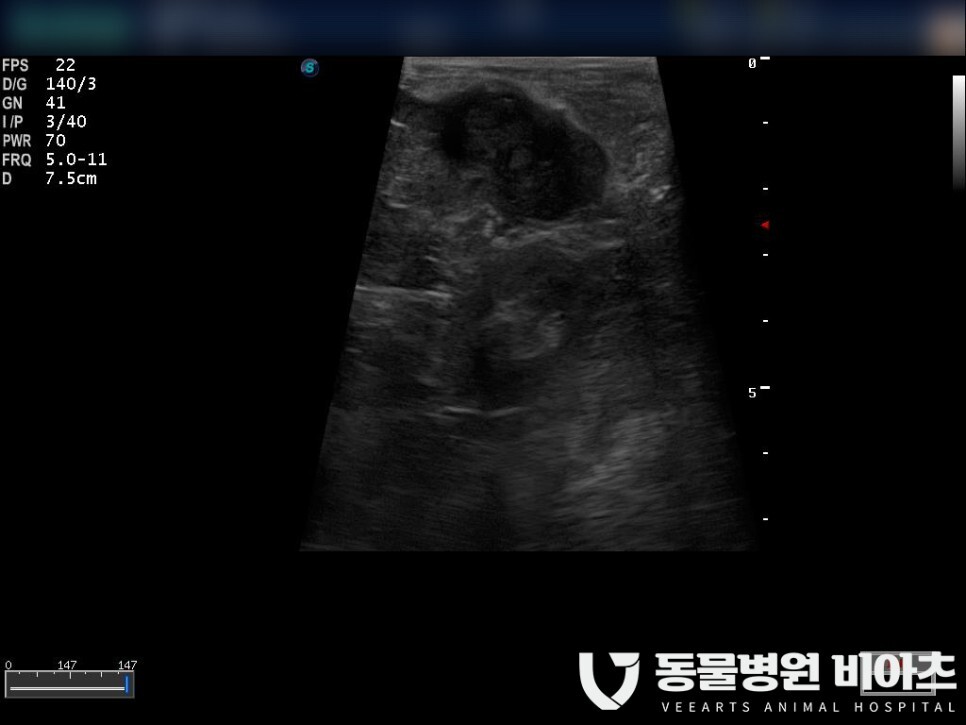

절제된 비장입니다.

비장을 절제한 후 확보된 공간으로 보이는 "간"입니다.

비장은 아주 깔끔하게 절제가 완료되었습니다.

하얀색으로 표시한 부분이 종양입니다.

크기는 약 3cm 정도였습니다.